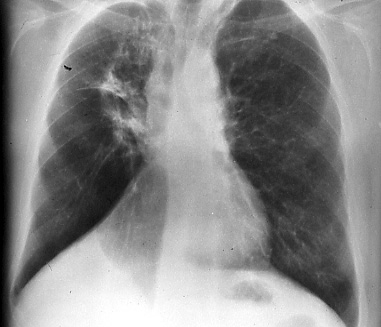

Fig.

2: Posterior-anterior

chest radiograph. Well established

changes of radiation pneumonitis

are present in the right

5 months after completion

of therapy, rTX. |